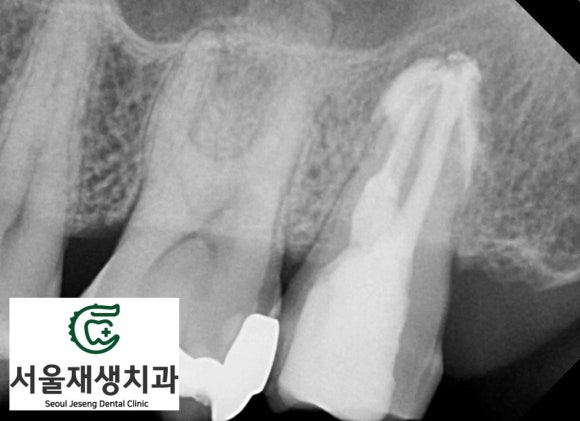

치아의 독사진을 촬영해봅니다.

단체사진보다 더 풍부하고 디테일한 정보를 줍니다.

일견 잘 되어 있는 치료처럼 보이지만,

밀도가 깊이가 부족해보입니다.

치아 내의 신경조직 잔사가 남아서 염증을 일으킨 것으로 보입니다.